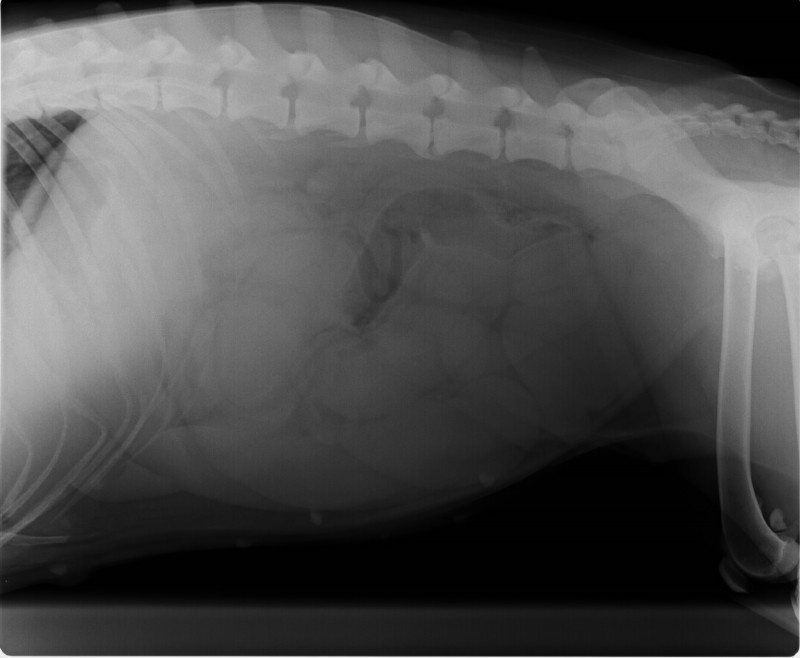

• Trächtigkeitsuntersuchung mittels Ultraschall

• Geburtshilfe und Welpenbetreuung

• Kaiserschnitte unter schonender Inhalationsnarkose